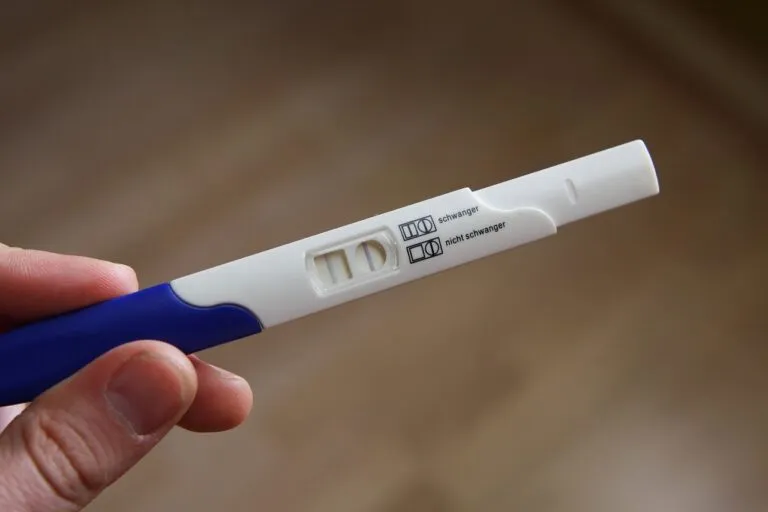

Pertes sanguines pendant la grossesse : normal ou alarmant?

Comment repérer les signes d’une grossesse extra-utérine ?